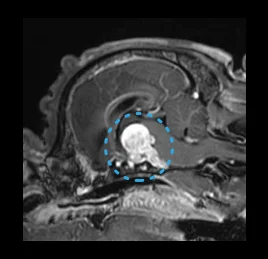

• 뇌하수체 종양

• 뇌종양

• 두개부 질환

이도의 염증, 내이염, 중이염, 외이염,

두개부 종양, 침샘류